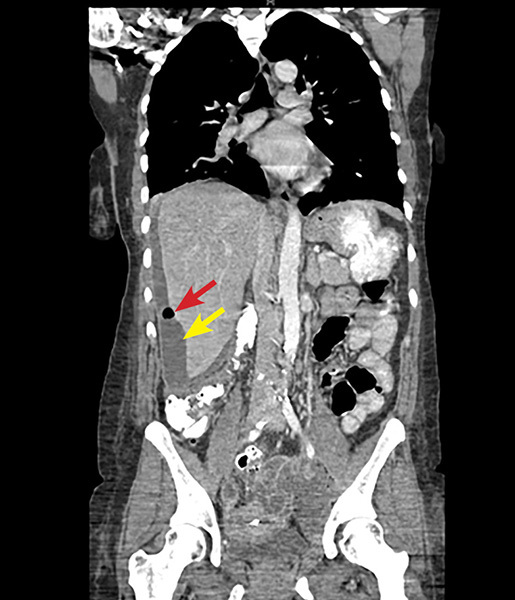

A definitive diagnosis is made laparoscopically by visualizing adhesions resembling violin strings or by hepatic capsular biopsy to identify causative organisms. Noninvasive diagnostic modalities, such as ultrasound, may show fluid collections and widening of the subphrenic area between the liver and the diaphragm. On CT scan, hepatic capsular enhancement may be seen. (See Figure 3.) Typically, a CT scan of the abdomen and pelvis is performed using a portal venous phase scan. However, recent studies have found that dynamic/biphasic abdominal CT scan using an additional arterial phase scan demonstrates increased sensitivity than portal venous phase alone by showing much greater depiction of perihepatic enhancement.36 Antibiotic treatment of FHCS involves the same antibiotic regimen as for uncomplicated PID.29

Figure 3. Coronal CT Scan Shows an IUD in the Mid Pelvis with a Left Adnexal Abscess and a Perihepatic Subcapsular Abscess with Air |

Perihepatic subcapsular abscess indicated by yellow arrow. Air indicated by red arrow. CT: computed tomography; IUD: intrauterine device Image courtesy of Basil Hubbi, MD, Department of Radiology, Rutgers New Jersey Medical School. |